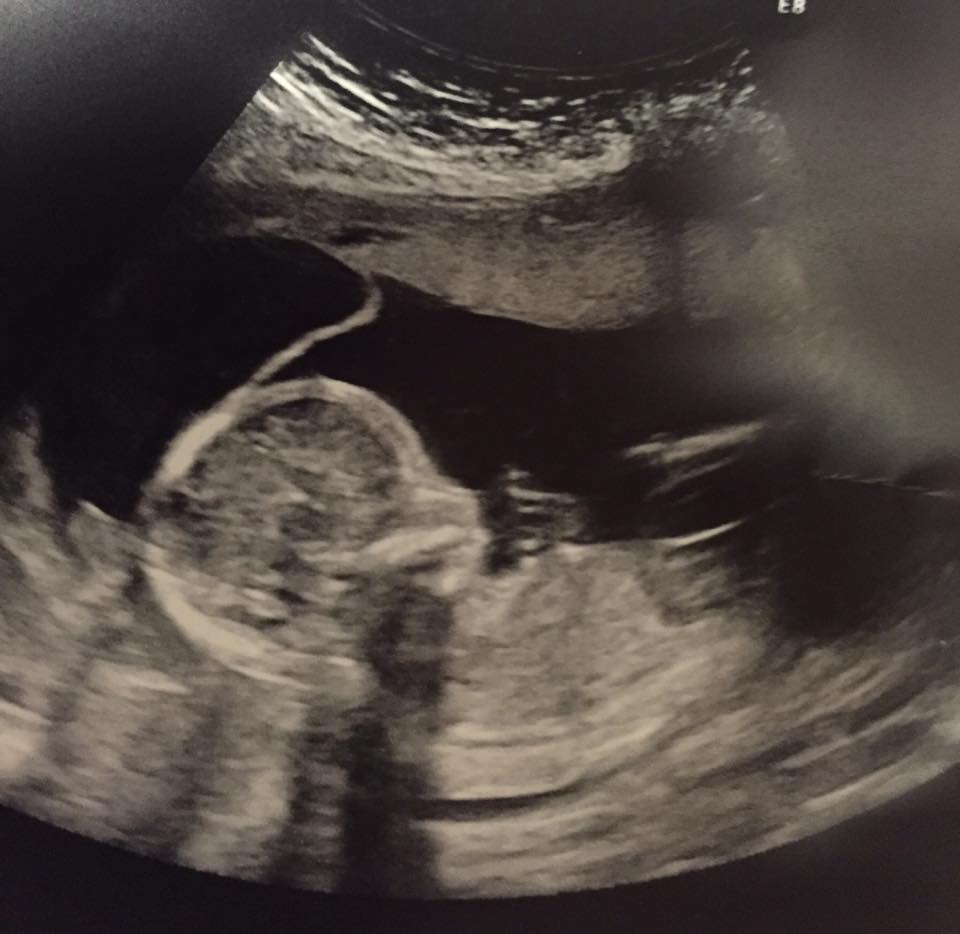

She braced herself for devastating news… but instead, she received life-changing news: the ultrasound revealed two boys and a girl—Courtney was pregnant with triplets.

At 25 weeks into the pregnancy, another tragedy occurred. One of the babies no longer had a heartbeat.